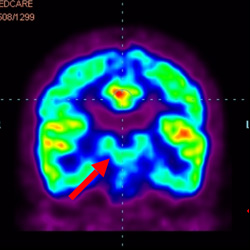

細(xì)胞治療前 PET CT 掃描顯示神經(jīng)組織中的藍(lán)/黑色區(qū)域,表明腦癱引起的大腦損傷。

腦癱細(xì)胞療法, 腦癱治療

細(xì)胞治療后,藍(lán)色和黑色區(qū)域減少,并且看到更活躍的區(qū)域。這表明損傷減少并改善了大腦功能。

這證明細(xì)胞療法是治療腦癱兒童安全有效的方法。細(xì)胞療法可以更新大腦損傷的核心,并且可以通過 PET CT 掃描來(lái)監(jiān)測(cè)大腦的改善情況。這些細(xì)胞療法與標(biāo)準(zhǔn)治療一起促進(jìn)腦癱兒童的生長(zhǎng)和改善。